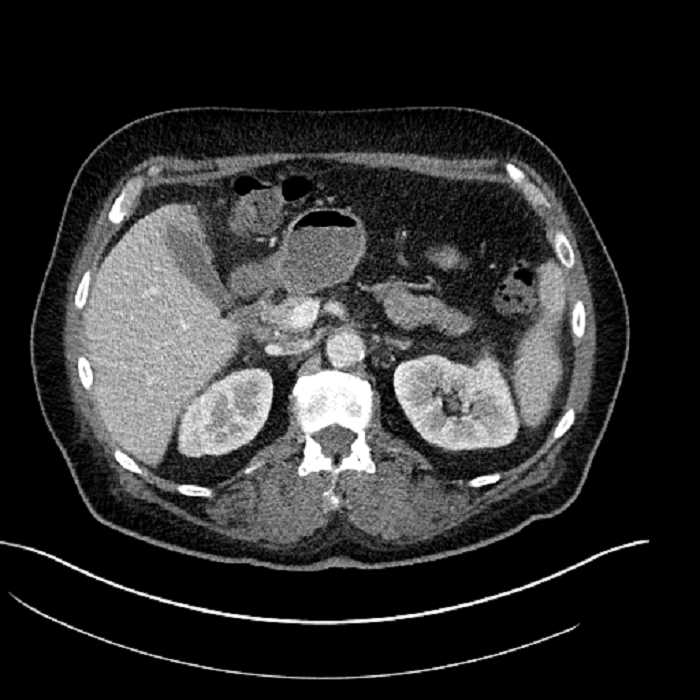

• Mild mural thickening of a segment of the sigmoid colon with adjacent fat stranding and a 1.5 cm fluid and gas collection along the tip of an inflamed diverticulum

• Loss of the normal fat plane between this collection and adjacent loops of small bowel, which demonstrate mural thickening

• No bowel obstruction

Acute sigmoid diverticulitis complicated by a small contained perforation and a large abscess in the right hepatic lobe. Additional small subcapsular abscesses along the anterior margin of the left hepatic lobe.

Additionally, loss of the normal fat plane between the peridiverticular collection and adjacent thickened loops of small bowel raises the potential for an enterocolonic fistula.

Hepatic abscess showing the double target sign with low density internally surrounded by a thin inner enhancing rim (red arrow) and ill-defined outer low density rim (yellow arrow). Blue arrow indicates an internal septation. Red arrows: additional smaller subcapsular abscesses. Red arrow: focal contained perforation associated with diverticulitis.